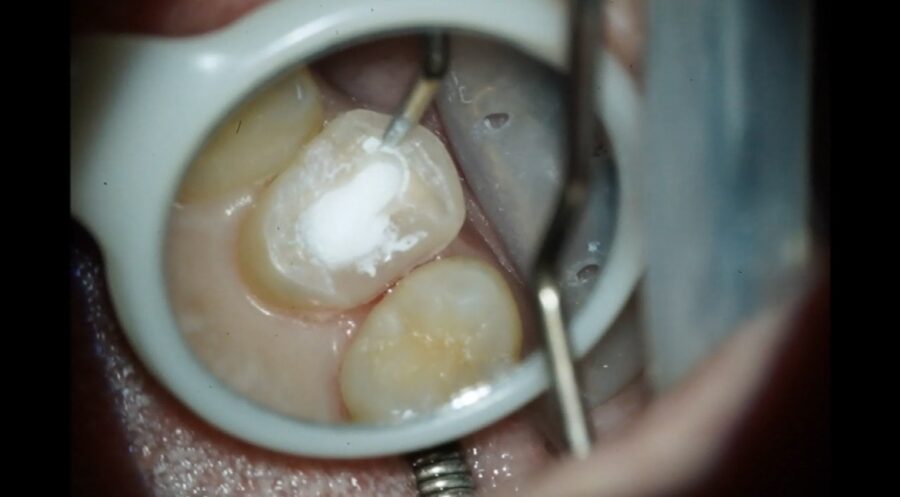

MTAセメント詰めた後↓ ↓ ↓

⭐︎MTAセメント特徴

・生体親和性が高い

・封鎖性が優れてる

・殺菌作用が高い などがあげられます。